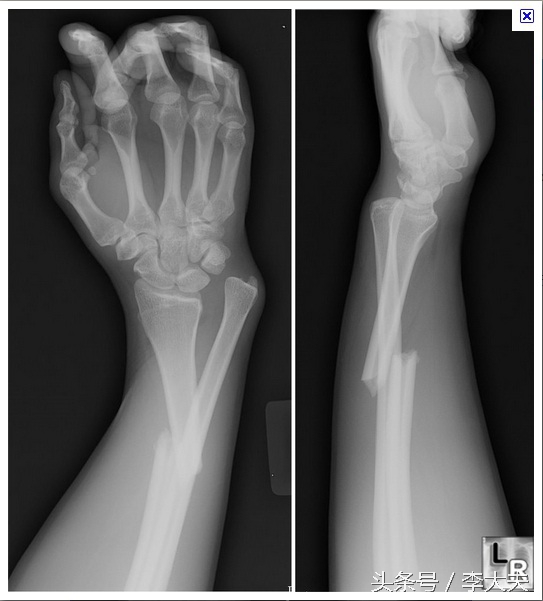

上肢前臂双骨折

上肢双骨折X线片